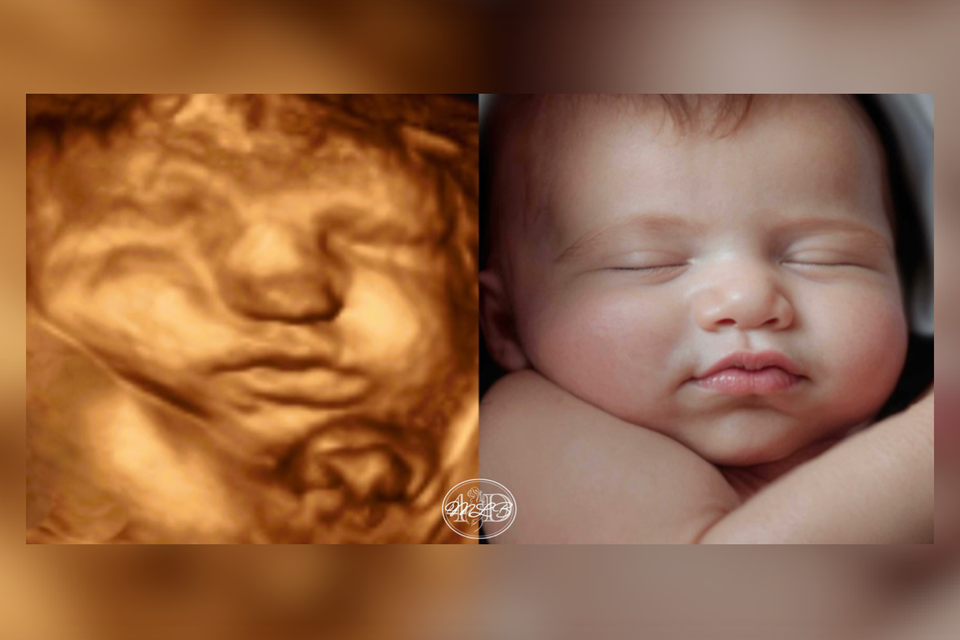

Most Realistic & lifelike photo you can get until the arrival of your little one. Using the newest technology to change your 3d/4d photo into something more realistic without changing any of your baby's features.